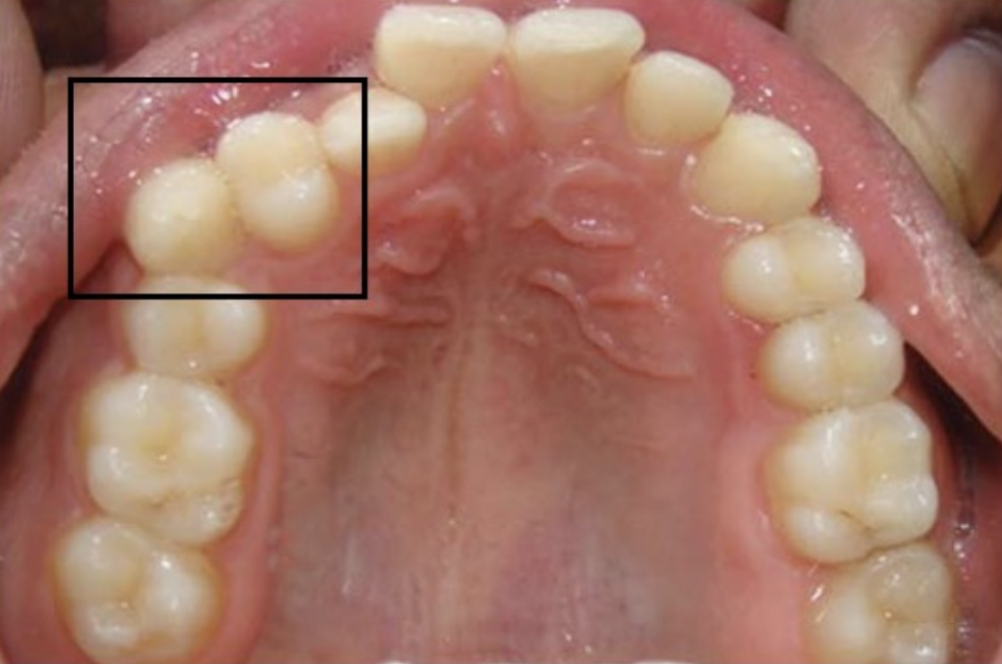

下列何者最常發生牙齒萌出位置呈現“錯位”(transposition)的情形?

(A)上顎犬齒與第一小臼齒